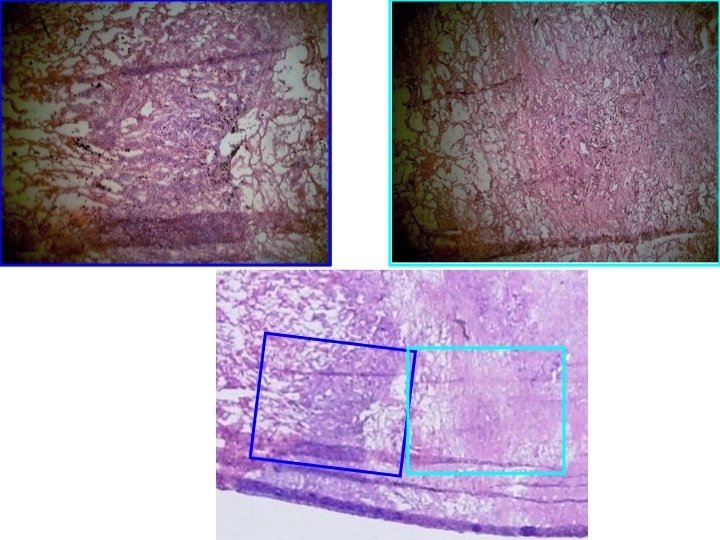

CR-39 ANALYSIS Histological samples on CR-39 detectors and corresponding image of samples after irradiation.

Image-Pro Plus © Microscopic Image Automated Analysis for hole area study and counting